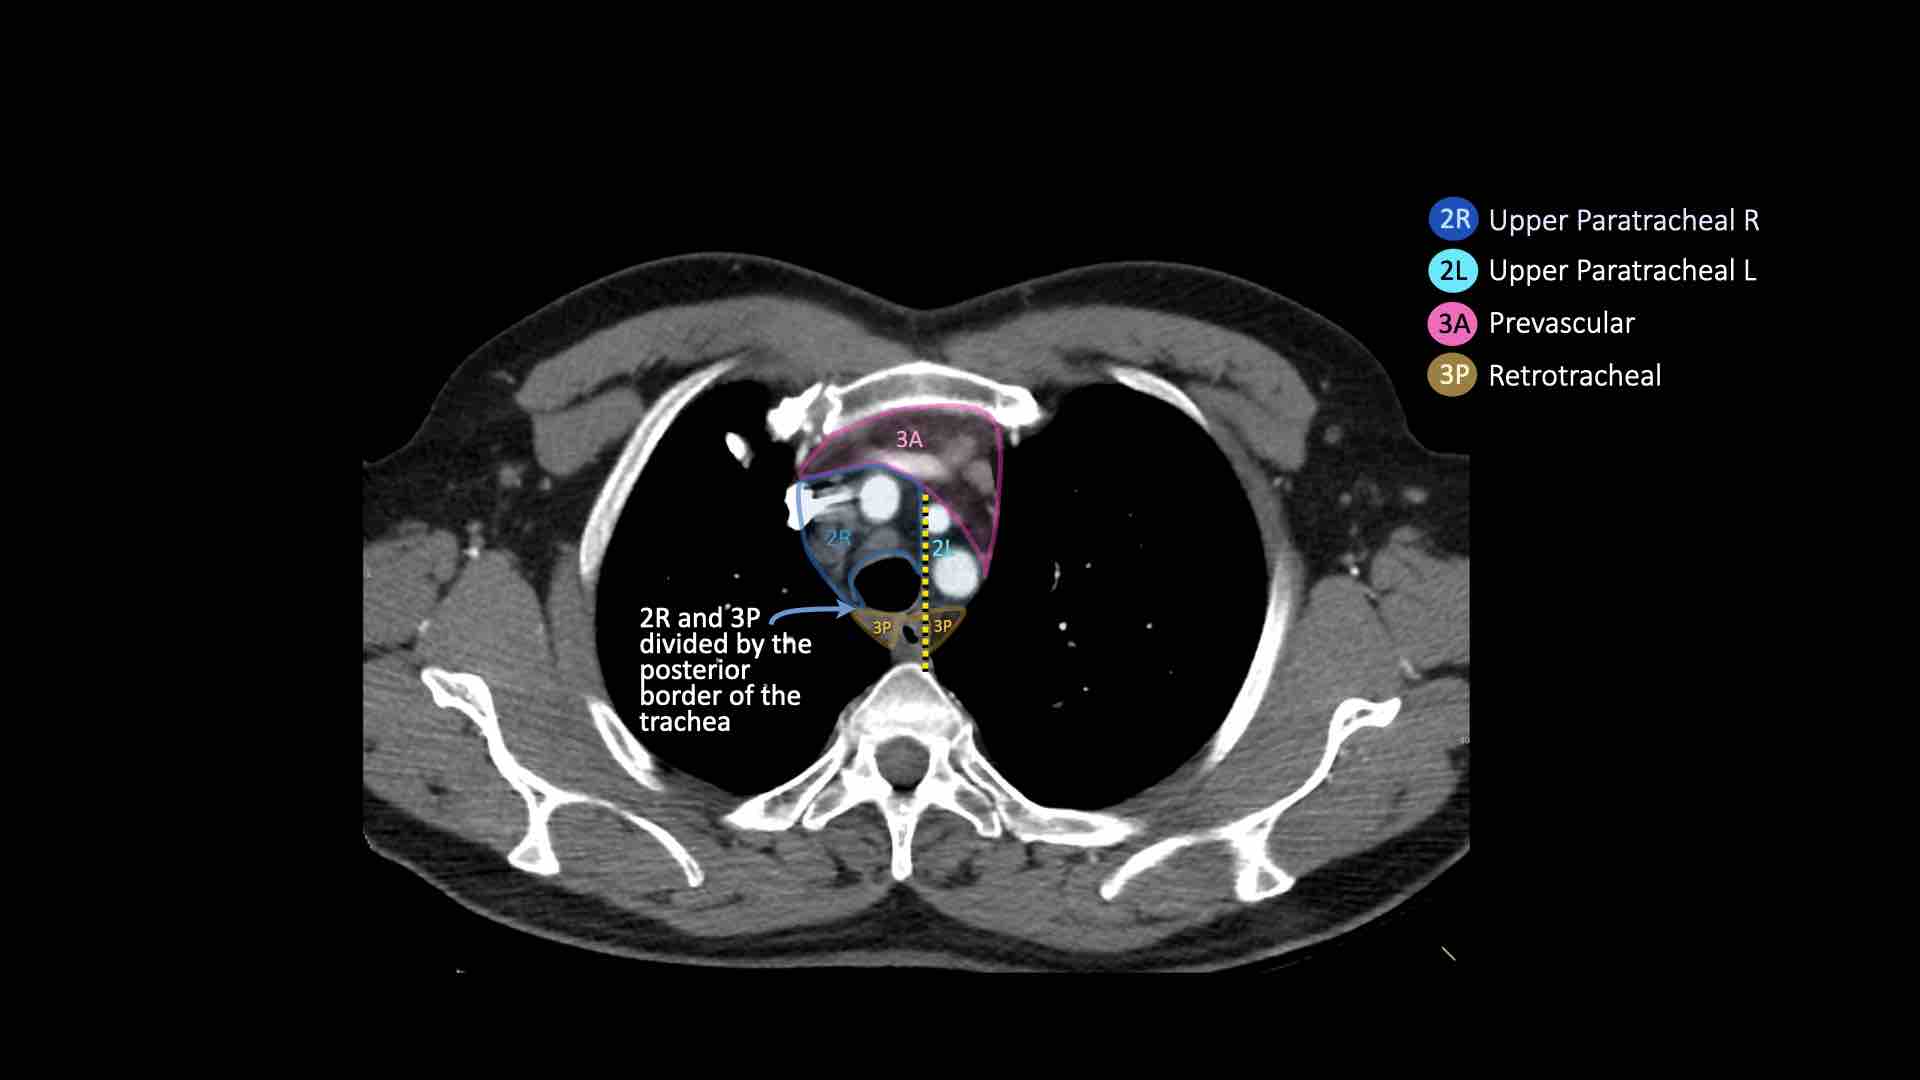

3A.Trước mạch máu

Các hạch này không tiếp giáp với khí quản như các hạch ở nhóm 2, mà nằm ở phía trước các mạch máu.

3P.Trước cột sống

Các hạch không tiếp giáp với khí quản như các hạch ở nhóm 2, mà nằm sau thực quản, tức là ở vị trí trước cột sống.

2R. Hạch cạnh khí quản trên bên phải

Hạch nhóm 2R trải dài đến bờ bên trái của khí quản.

Ranh giới trên: bờ trên cán ức.

Ranh giới dưới: giao điểm của bờ dưới tĩnh mạch vô danh (tĩnh mạch tay đầu trái) với khí quản.

2L. Hạch cạnh khí quản trên bên trái

Ranh giới dưới: bờ trên quai động mạch chủ.

3. Hạch trước mạch máu và trước cột sống

Hạch nhóm 3 không nằm kề khí quản như hạch nhóm 2.

Chúng có thể là:

3A nằm phía trước các mạch máu, hoặc

3B nằm phía sau thực quản, vốn nằm ở vị trí trước cột sống.

Hạch nhóm 3 không thể tiếp cận bằng nội soi trung thất.

Hạch 3P có thể tiếp cận bằng siêu âm nội soi (EUS).

- Cạnh khí quản trên: phía dưới xương đòn, bên phải nằm trên giao điểm của bờ dưới tĩnh mạch vô danh (tĩnh mạch tay đầu trái) với khí quản, bên trái nằm trên cung động mạch chủ

- Trước mạch máu và Sau khí quản: nằm trước các mạch máu (3A) hoặc trước cột sống (3P)